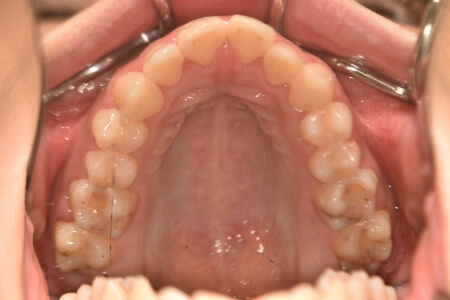

開咬(抜歯)【2245】

動的治療終了時

症例 症例 症例 症例

治療内容の詳細 初診時18歳の女性で、前歯がでている事を気にされ来院されました。

検査の結果、開咬を伴うアングルⅡ級1類不正咬合と診断しました。

治療としては、上顎第一小臼歯を抜歯の上、セルフライゲーションブラケット装置(デーモンシステム)とマウスピース型矯正装置(インビザライン)で配列を行いました。顎間ゴムの協力もあり、開咬がきれいに改善されました。

この際、上顎に歯科矯正用アンカースクリューを設置し上顎前歯部後退時の土台としました。